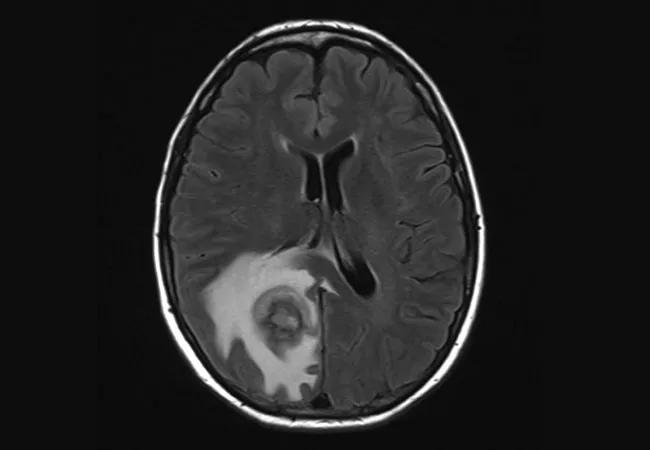

She underwent an MRI of her brain (image at top), revealing a single 2.4-cm peripherally enhancing right parietal lobe lesion with centrally restricted diffusion and significant adjacent vasogenic edema with local mass effect. Chest CT showed a few indeterminate sub-centimeter pulmonary nodules and mild interstitial fibrosis. CT of the abdomen and chest was normal.

A biopsy of the right parietal lobe mass was performed and confirmed a diagnosis of diffuse large B-cell lymphoma associated with Epstein-Barr virus (EBV) (Figure). As a result, her MMF treatment was discontinued.

Image at top is reproduced from Chatterjee et al., Joint Bone Spine. 2020:87:163-166. Copyright © 2020 Elsevier Masson SAS. All rights reserved.